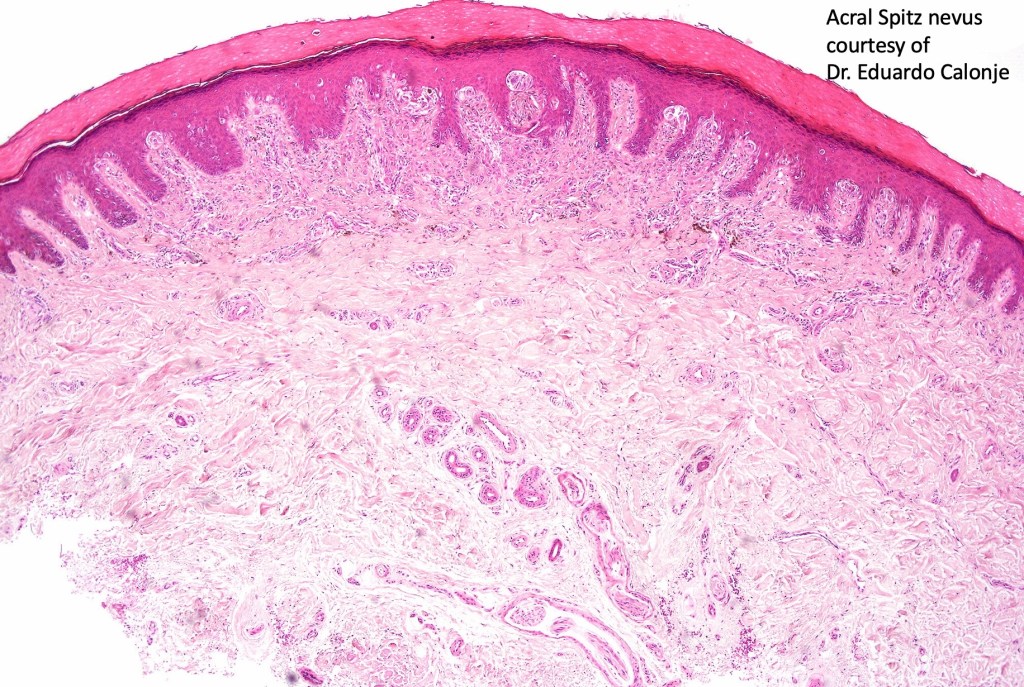

•Sharply circumscribed (begins and ends with a nest), symmetrical dome-shaped lesion. Symmetry is both horizontal and vertical (see image below)

•Wedge-shaped with the base uppermost or sometimes plaque-shaped silhouette

•Matures with depth-often best recognized at scanning/low power magnification & readily confirmed with S100 or MART1

•Hyperkeratosis & acanthosis, sometimes very marked

•Superficial vascular ectasia very frequently present